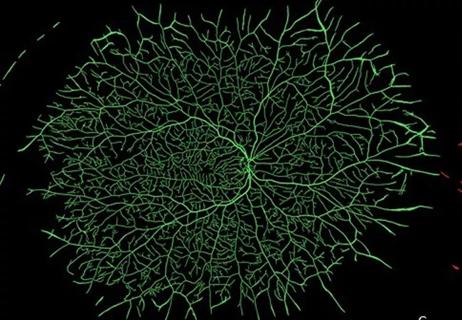

Why and How Hyperoxia Leads to Growth Suppression in Retinopathy of Prematurity

New study points to retinal metabolic remodeling and hepatic nitrogen imbalance